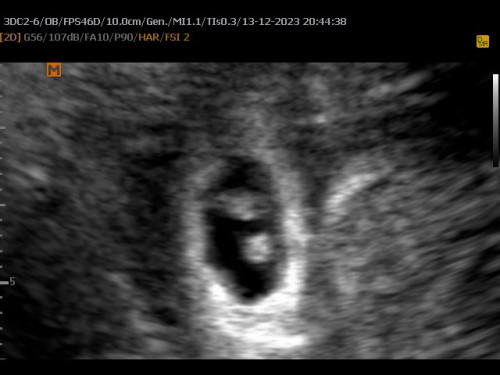

มีสิทธิได้น้องแฝดไมค่ะ

หมอบอกว่ายังไม่แน่ใจเลยค่ะ ตอนเจอ6w2bค่ะ

ยังเล็กมากเลยค่ะ สัก 12 วีคน่าจะเห็นได้ชัดค่ะ ว่าแฝดมั้ย